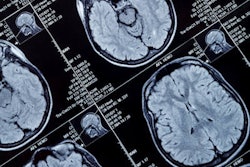

Researchers from Northwestern University and Massachusetts General Hospital/Harvard Medical School used MRI to compare the brains of 18- to 25-year-olds who reported smoking marijuana at least once per week with those with little to no history of marijuana use.

Among the 20 marijuana users, the nucleus accumbens -- a region of the brain associated with reward processing -- was larger and altered in shape and structure, compared with the brains of the 20 nonusers.

In addition, the more marijuana users reported consuming, the greater the abnormalities in the nucleus accumbens and the amygdala, which is associated with emotion. The shape and density of both of these regions differed between marijuana users and nonusers.